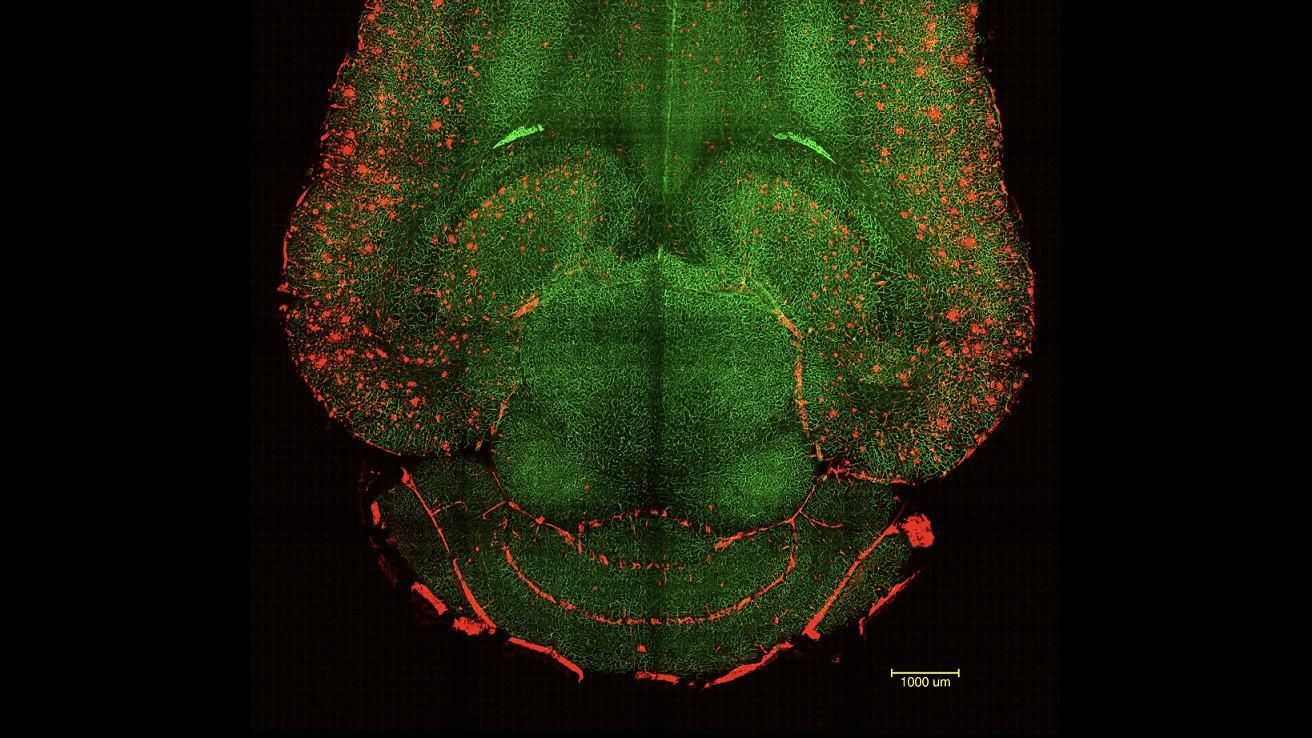

Imagen microscópica del cerebro de un ratón tratado con la nueva terapia basada en nanopartículas | IBEC

Un equipo científico co-liderado desde España por el Instituto de Bioingeniería de Cataluña (IBEC) y el Hospital Occidental de China de la Universidad de Sichuan (WCHSU), han logrado un avance prometedor contra el alzhéimer en modelos animales. La nueva terapia usa nanopartículas que actúan como fármacos activamente, no solo como transportadoras, para restaurar la función de la barrera hematoencefálica (BBB), esencial para eliminar toxinas del cerebro.

Tras administrar solo tres dosis, los investigadores observaron una reducción del 50-60 % en los niveles de proteína amiloide-β (Aβ) en el cerebro apenas una hora después de la inyección. Con el tiempo, los ratones tratados recuperaron comportamientos similares a los de animales sanos, incluso cuando ya presentaban deterioro cognitivo avanzado.

El secreto del éxito radica en que las nanopartículas no actúan directamente sobre las neuronas, sino que restablecen el sistema vascular cerebral. De esta forma, se reactiva la limpieza natural del cerebro al permitir el paso controlado de proteínas tóxicas hacia la sangre.